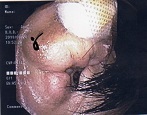

耳介皮下血腫 : 白血球数にこだわっています。

頭部・顔面の打撲・怪我|福岡市西区の脳神経外科 - はしぐち脳神経